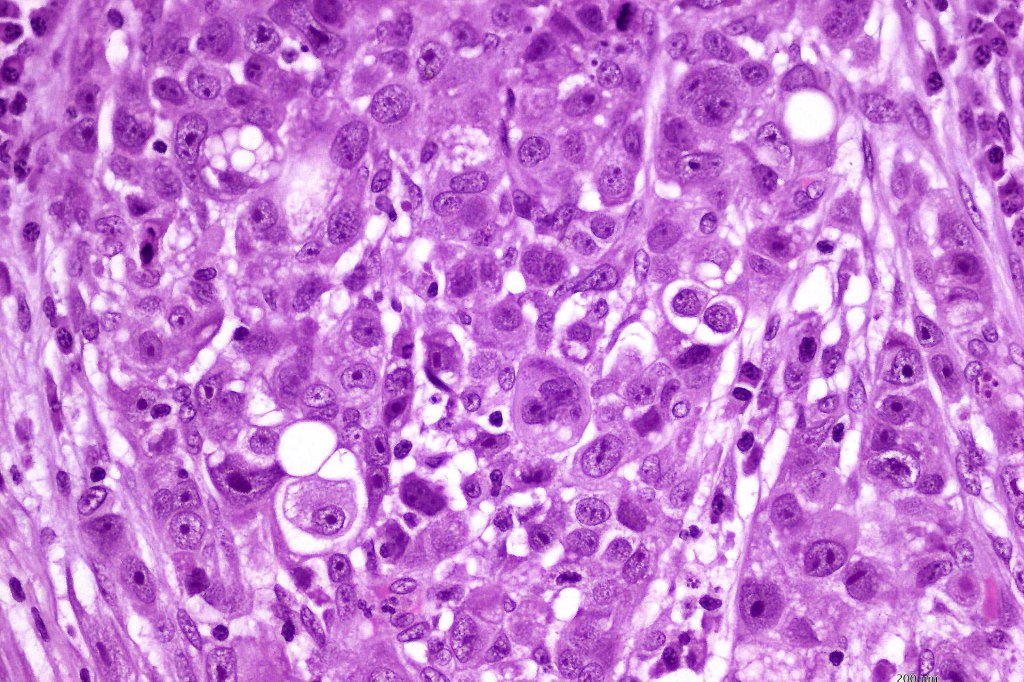

•Large cells with vesicular nuclei and often prominent nucleoli

•Decapitation secretion

•Variable pleomorphism, mitotic activity & atypical mitoses

•Variable necrosis

•Intracytoplasmic DPAS +ve granules